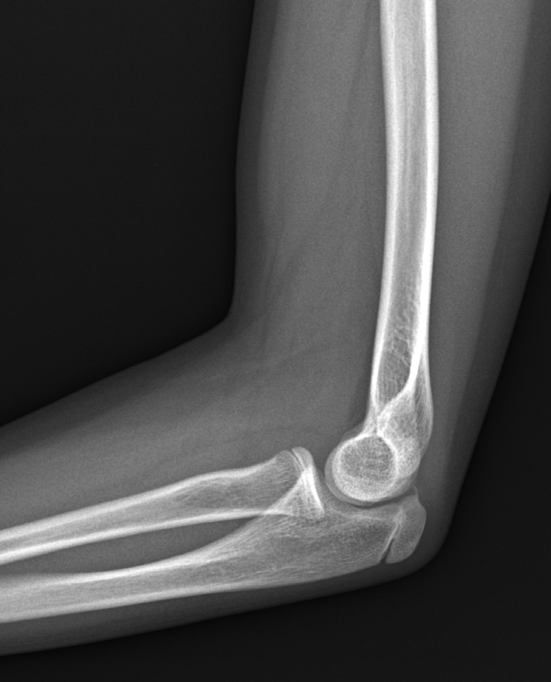

성장판 사진. 환아의 역연령 (실제 나이)는 만 10세 10개월이다. 뼈나이는 몇살일까?

"어머님, 지금 뼈나이는 12살~12살 6개월 정도 되어 보여요. 자기 나이보다 1년 반정도 빠른 거예요.

만약에 실제 나이와 뼈나이가 똑같이 1년 6개월 정도 차이나는 상황에서, 1년 정도 더 빨리 오셨다면, 치료를 해보는 쪽으로 저도 고려했을 거 같습니다. 하지만 지금은 아닙니다."

"만약에 치료를 하게 되면, 현재 성장판 정도를 봤을 때 2~3년 정도 치료 가능할 것으로 보여요.